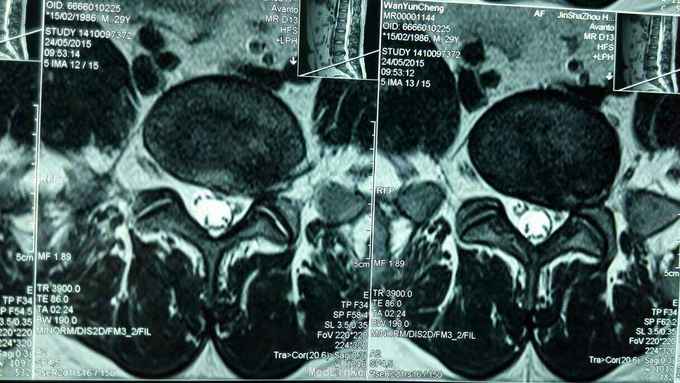

反复腰痛5年,再发5月,加重3天。 5年来反复出现腰部酸痛,未正规治疗,5个月前因腰痛不能下床,双下肢麻木,在针灸康复科住院治疗,疼痛减轻,出院休养,3天前再发腰痛,不能平躺,右下肢麻木入院。

步态正常,右侧椎间、椎旁压痛,右侧坐骨神经行程压痛,向下肢后缘放射,右侧髌腱反射、跟腱反射减弱,肌力正常。

腰椎间盘突出症,骶管囊肿 在神经阻滞麻醉下行,后路腰4~5椎间盘摘除术,骶管囊肿切开引流,神经根外膜松解术。 术后患者腰痛,右下肢麻木缓解。